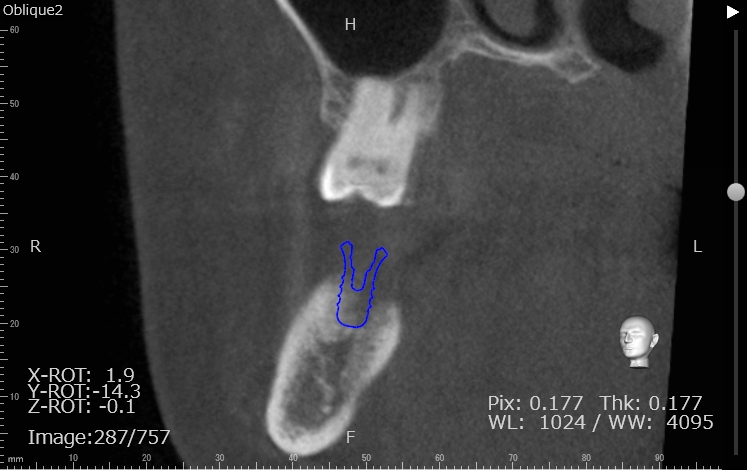

Case7

術前

術中

術後

| 治療名 | 抜歯即時インプラントとソケットリフトによる上顎臼歯部の修復症例 |

|---|---|

| 治療説明 |

歯の根が破折していたため抜歯が必要となり、患者さんとご相談のうえ、インプラントによる治療を選択しました。 ただし、インプラントを支える骨の高さが不足していたため、**上顎洞に骨を足す“ソケットリフト”**を併用し、安全にインプラントを埋入しました。 |

| 治療回数・期間 | 約3ヶ月 |

| 副作用とリスク |

・入れ歯や従来のブリッジと比べて、治療期間が長くなる傾向があります。 |

| 料金(税込) | 小規模GBR:110,000円 ソケットリフト:165,000円 インプラント一次手術:220,000円 二次手術:55,000円 上部構造〈セラミック〉:165,000円 合計:715,000円 |